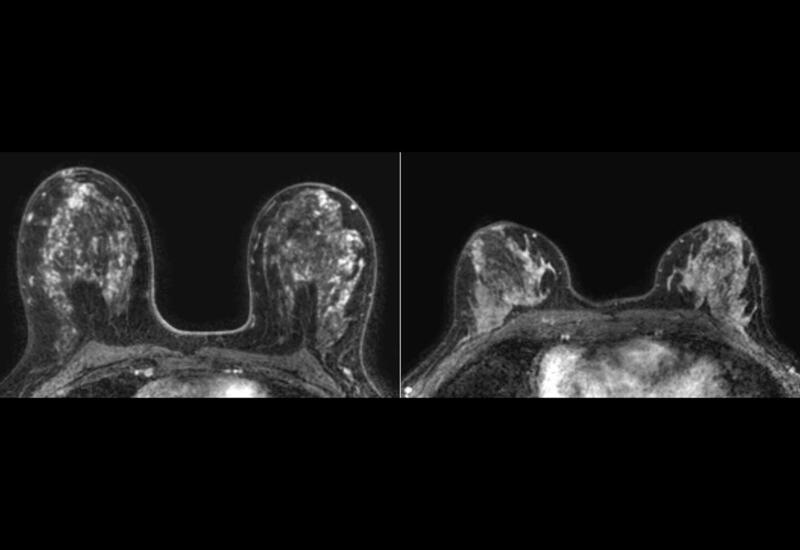

В экспериментах на мышиных моделях и клетках рака молочной железы человека ученые выяснили, что присутствие бактерии ускоряет рост опухоли и усиливает распространение раковых клеток в легкие. При локальном воздействии в тканях молочной железы возникали гиперпластические и метапластические изменения - это нераковые состояния, при которых клетки либо чрезмерно делятся, либо меняют свой тип. Такие процессы сопровождались воспалением и повреждением ДНК.